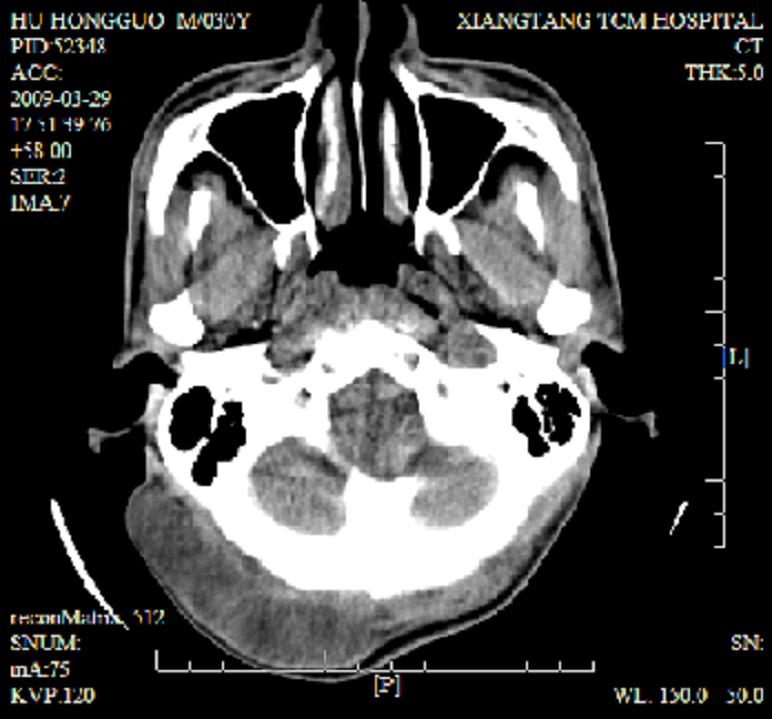

标题: CT19102:颈部肿块

男30y发现肿块3年

多处囊实性肿块,形态欠规则有一定形态,内见点状钙化,以囊变为主,增强后轻度强化,首先考虑神经源性肿瘤如鞘瘤,不除外脉管源性肿瘤如淋巴管瘤(见缝钻及囊性区域太多,如果合并感染完全可以这个影像表现),和海绵状血管瘤,但是血管瘤不太支持因为强化特征和病灶形态不典型.

右侧椎前间隙后部肌间、皮下囊性为主病变,可见分隔和点状钙化,分隔和壁呈轻度环形强化,大部分无强化。形态不规则,有钻缝特点。考虑1 淋巴管瘤合并感染2 血管平滑肌脂肪瘤3 表皮样囊肿4 不除外海绵状血管瘤。